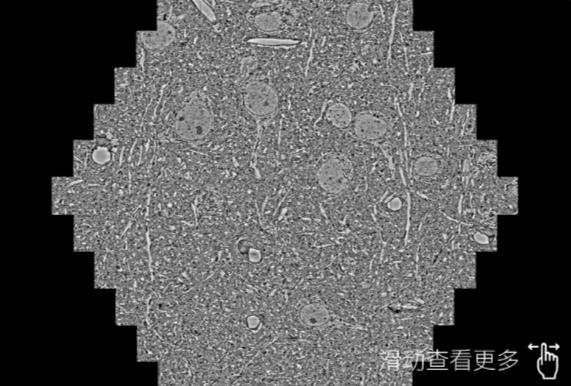

鼠脑切片。左图使用鸡西蔡司鸡西扫描电镜MultiSEM706对165μmx143pm面积区域成像,耗时仅需1.5秒。右图为鼠脑切片中30μm区域放大效果。样品由芝加哥大学B.Kasthuri提供。